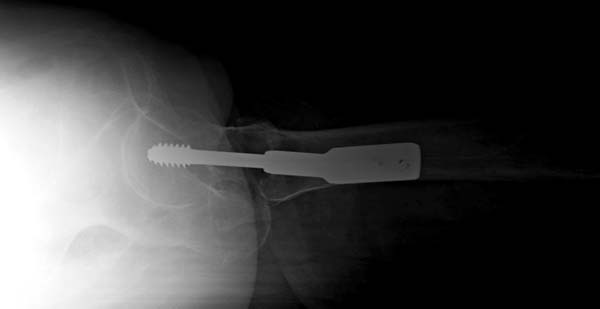

Прилагается п/о рентген снимок.

На этой проекции все неплохо, а вторая?

Сегодня сделал р-снимок, как было сказана,

но получилось не качественная, р-аппарат "Арман" старенький, недавно получили новый "Сименс" , скоро запустим!

То-что получилось отправляю, за качества извиняюсь!